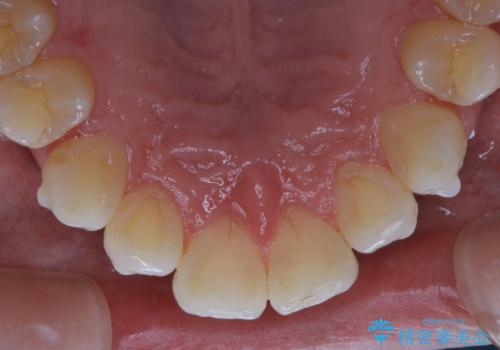

- インビザライン矯正治療中の方です。アタッチメントの周りの汚れが気になるとのことで、PMTC30分コースを行いました。

インビザライン矯正治療はマウスピースを長時間使用するため、歯石や汚れなどが付着したままだと、フィットが悪くなったり、口臭が強く出たりする原因につながることもあります。

ぜひ定期的なクリーニングをおすすめします。